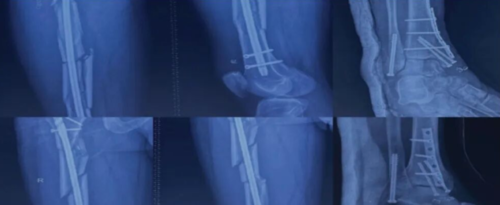

图 3 A 一名 80 岁女性患右侧股骨干骨折(AO31-A1 型)。B 在进行 PFNA 治疗之前首先实现骨折的解剖复位,然后用单根有限接触式钢丝固定;C 术后 70 天随访显示骨折顺利愈合